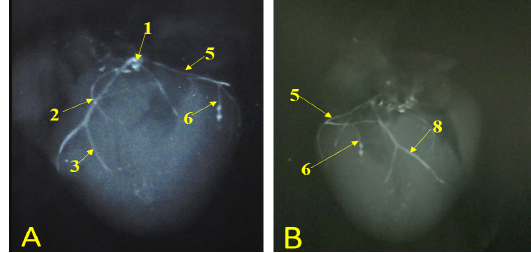

Showing radiographic images for division of the left coronary arteries, A- showing the left coronary artery. B- showing the branches of left circumflex artery.